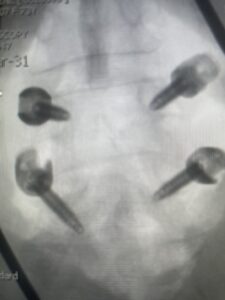

Fig 6: AP and lateral fluoroscopic images demonstrating pedicle screw placement in L3-4 fusion for spondylolisthesis.

Another patient is a 62 year-old female with progressive low back pain and right leg pain and numbness that radiates to the top of her foot. She tried physical therapy and epidural injections. MRI demonstrated severe L3-4 stenosis and a grade 1 spondylolisthesis (Fig 4). There was L5-S1 and L4-5 disc collapse with modic end-plate changes. Biomechanically because of the significant degeneration of these disc spaces which stiffened the L4-S1 segment more stress was placed on the L3-4 segment, resulting in significant premature degeneration and compensatory stenosis and segmental instability. The MRI also showed pathologically, because of the slip, the L3 inferior processes were more anteriorly oriented and hence contributing to the majority of the lumbar canal compromise. Note the more sagittally-oriented facets in this case compared to the prior case (Fig 5). The patient underwent a decompressive laminectomy with attention of removing the inferior processes of L3 to fully decompress the canal. We also performed an L3-4 fusion with instrumentation (Fig 6). The patient had an uneventful postoperative course with improvement of leg pain. Of note with relief of the disabling leg pain patients are generally very happy. Patients can often manage their low back pain; it is the leg pain that they just can’t tolerate.